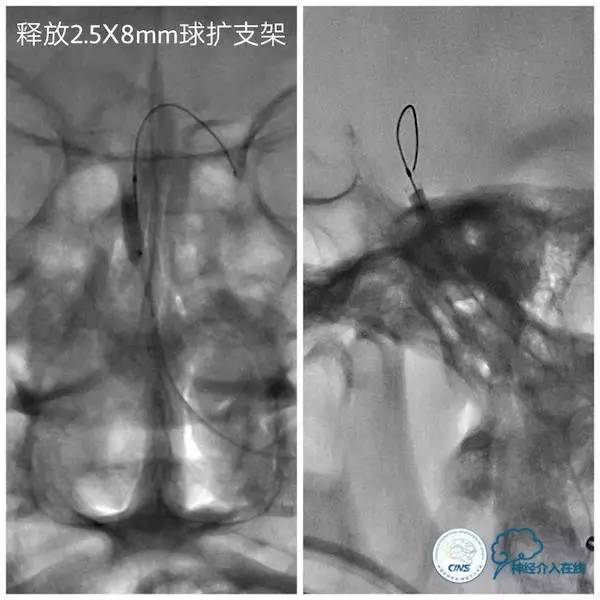

扩张后沿微导丝送入Apollo支架(2.5mm×8mm),释放支架后造影显示支架贴壁良好,狭窄明显改善,前向血流TICI3级(图9,10)。

图9

图10